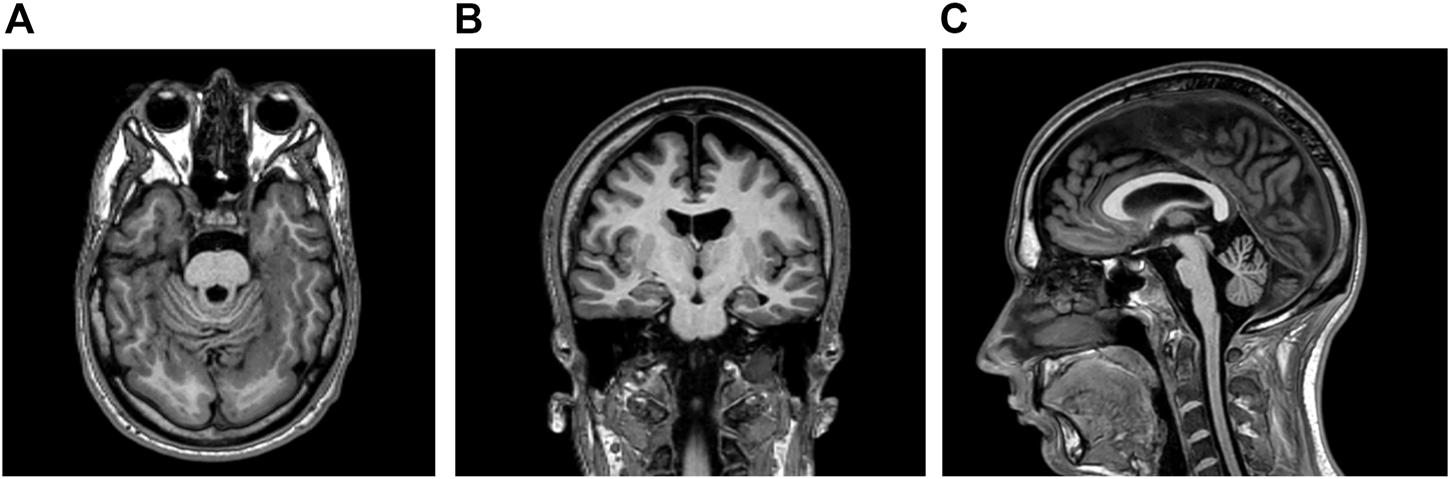

This right-handed, 28-year-old Caucasian man had an unremarkable antenatal and perinatal history. His parents were non-consanguineous and healthy. His older sister did not have known medical conditions. No familial history of genetic, metabolic, or neurological diseases was reported. Educational support was necessary during school years. At the age of six, the patient started to experience daily seizures—often several times a day - with different semeiology: 1) episodes of symmetrical myoclonic spasms of the upper limbs; 2) involuntary movements of both eyes in different directions, followed by behavioural arrest, and impaired awareness with unilateral/bilateral manual automatisms (i.e., manipulating, nose-wiping, and hair-fixing). Multiple antiseizure medications (i.e., lamotrigine, phenobarbital, nitrazepam, vigabatrin, clobazam, topiramate, lacosamide, levetiracetam, oxcarbazepine, brivaracetam) were unsuccessfully administered. The patient came to our attention at the age of 23, when he was taking rufinamide 3,200 mg/day, valproate 1,000 mg/day, and carbamazepine 800 mg/day. Daily seizures with different semeiology (myoclonic, atonic, focal motor, and bilateral tonic-clonic seizures) were reported. Neurological examination was unremarkable except for divergent strabismus in the left eye. No dysmorphic features were identified. Interictal electroencephalogram showed spikes, polyspikes, and polyspike-and-waves localized in the occipital regions. Brain magnetic resonance imaging (MRI) was also performed revealing bilateral temporal and occipital polymicrogyria; atrophy of the pons and cerebellum was also detected (Figure 1). Neuropsychological assessment revealed moderate intellectual disability (ID) with a low intelligence quotient (I.Q. = 48).

FIGURE 1

(A,B) Brain magnetic resonance imaging (MRI) showing bilateral polymicrogyria in temporal and occipital lobes (T1-weighted axial and coronal sequences respectively) (C) Atrophy in pons and cerebellum was detected in the T1-weighted sagittal sequence.